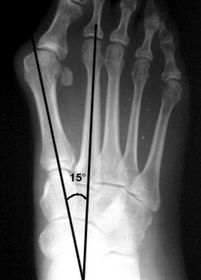

What angle is this? Is this normal or abnormal? | 1st intermetatarsal angle Abnormal. Greater than 9 degrees is abnormal. Usually due to metatarsus primus varus |